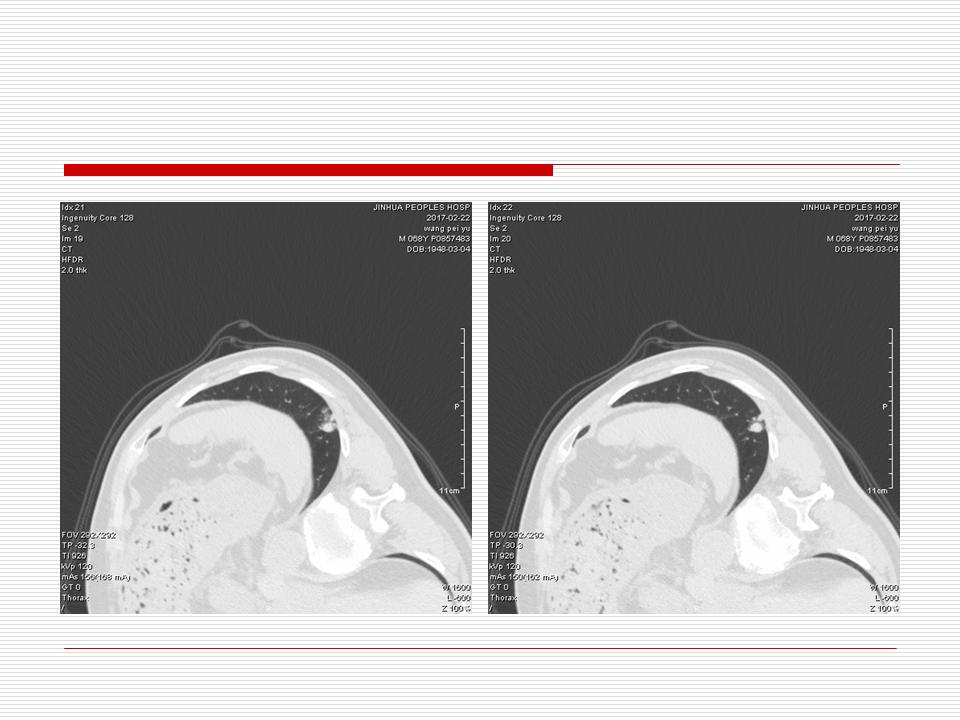

肺部阴影永恒且最重需要鉴别的是:到底是炎症还是肿瘤?但临床的病例中的影像表现难以界定或有些肿瘤特征,同时又有些炎症特点是非常常见的情况。作为临床医生我们怎么去总结分析,并找到之所以是炎症或之所以是肿瘤的细微差别或特点非常重要,也非常有用。2019.12.7浙江省2019年胸心外科学学术年会在宁波召开时,我的临床病例分析与经验总结<那些像肺癌的炎症与像炎症的肺癌>获得在大会交流的机会,以下为该PPT的内容,与你分享,希望对同道有益,有借鉴与启迪。若有探讨与进一不完善的建议,欢迎文末留言讨论: